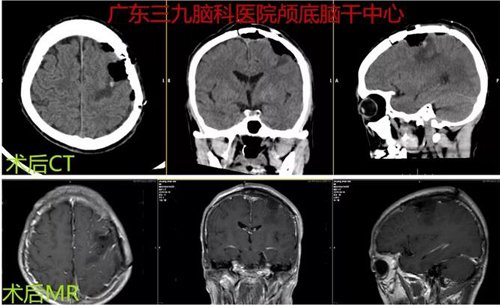

图3:术后CT及MR示左侧顶部非典型脑膜瘤切除术后改变,原病变已切除